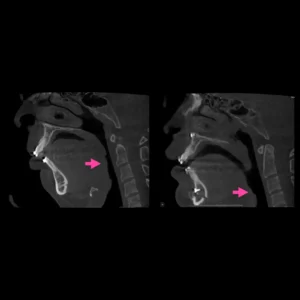

Trastornos de la articulación temporomandibular (ATM)

Diagnóstico y tratamiento de dolor, chasquidos o bloqueo al abrir la boca, causado por problemas en la articulación.

Disfunción de articulación Temporomandibular

Es la segunda afección musculoesqueletica crónica mas común después del dolor lumbar crónico; puede afectar las actividades diarias básicas como comer y hablar, el funcionamiento psicosocial y la calidad de vida de una persona.

Las articulaciones temporomandibulares desempeñan un papel crucial en la masticación, en la expresión verbal y emocional.

Los trastornos incluyen síntomas de dolor orofacial.

Los nuevos criterios ofrecen un protocolo de evaluación basado en detectar trastornos intraarticulares que requieren historia clínica, exploración física, complementadas con imágenes para un diagnóstico y tratamiento definitivo.

Tratamiento: Artrocentesis